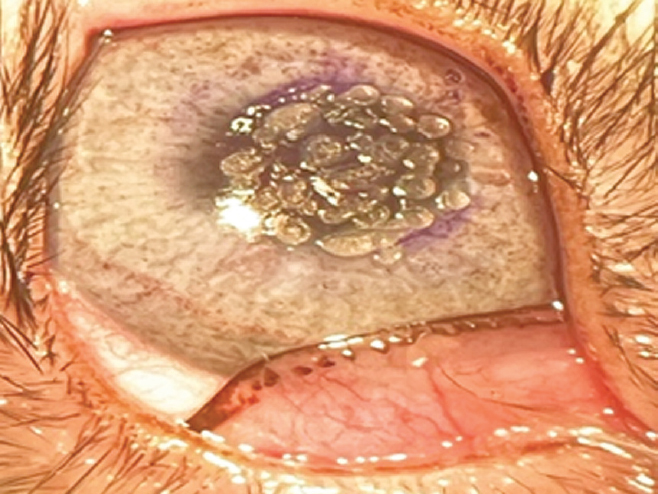

В исследовании использовали аппарат Jett Plasma Lift Medical (Compex, Чехия) в режиме фульгурации, основанном на бесконтактном равномерном воздействии на ткань пучком плазмы (электроискровое прижигание). Его действие достигается за счёт непрерывного искрового разряда в сочетании с тепловой энергии. Прибор имеет разные мощности при изменяемой интенсивности. Интенсивность (режимы) от 1 до 8, мощность от 0,026 до 1,817 Вт. Наносили коагуляты в центральной зоне роговицы кролика (рис. 1) в различных режимах от 5 до 8.

Рис. 1. Коагуляты на роговице кролика, режим 8

Fig. 1. Coagulates on the rabbit cornea, mode 8